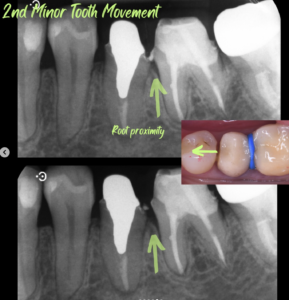

ここからも、補綴専門医の腕の見せ所です。まずは、歯質を挺出させ、虫歯になっていない部分を歯肉上に牽引します。ゴムで引き上げながらFiberotomyとRoot planingを併用して約1ヶ月で垂直的移動が終了(1ヶ月)。矯正的に引き上げると周りの骨や歯肉が一緒に上がってきますので、矯正後に外科的に取り除くことが必要です。これを避けるために、ゴムの交換時に一緒に歯周靱帯を切断し根麺を滑沢にしてあげます。そうすることにより、歯の根だけ引き上げることが可能です。従って、追加の外科処置は必要なくなります。その後、歯根の近接も解消しなければならないので、矯正用の歯間ごむで水平的に移動させました(2週間)。最後に、後戻りを防ぐため2−3ヶ月固定期間を設けて、歯冠部の補綴処置に進みました。